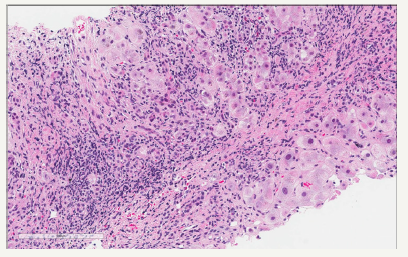

Most published series found that the most common type of hepatic primary lymphoma is diffuse large B-cell lymphoma, comprising 45% of the cases, followed by Burkitt lymphoma, lymphoblastic lymphoma, follicular lymphoma MALT lymphoma mantle cell lymphoma and T-cell lymphoma [1]. The cells are large with vesicular nuclei and prominent nucleoli. (Figure 1) from a hepatic mass biopsy is showing poorly differentiate malignant cells. This is required the application of proper immunohistochemical markers including CD45, CD20, CD5, CD10, CD79a, CD30, cyclin D, bcl2 and bcl6. The panel reveals lymphoma cells as the tumor cells were positive for CD45 lymphocyte marker. The cells were predominantly expressing CD20 (Figure 2), which is B-cell marker and support a diagnosis of large B cell lymphoma. Some subtypes of lymphoma like T-cell rich-B cell required molecular studies to establish the accurate diagnosis. Chronic lymphocytic leukemia/ small lymphocytic lymphoma tend to show portal infiltration. Other lymphoma type may show predominant diffuse infiltration [3-5].

Figure 2:B cell marker CD20 expression.